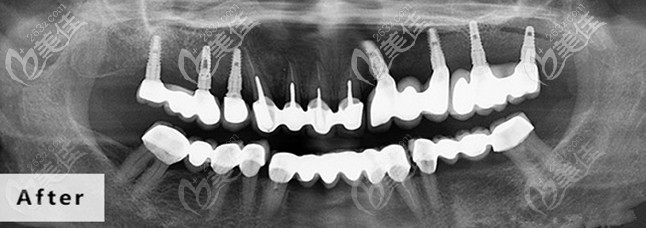

成都德道口腔成立于2016年,擁有占地面積約1600平方,地址位于:青羊區(qū)金鳳路19號(hào)附1號(hào),靠近青羊區(qū)金沙博物館,地理位置比較開(kāi)闊,門口有停車區(qū),停車比較方便。德道口腔設(shè)有種植科、正畸、修復(fù)科、綜合治療科、潔牙保健科、兒童牙科等診療室,每個(gè)科室都有??漆t(yī)生坐診,配置進(jìn)口的全景儀、牙椅、消毒、技工等牙科治療設(shè)備。德道口腔——智能口腔3.0診療體系:即刻用3.0種牙技術(shù):幫您當(dāng)天戴牙冠,完成種植牙手詳細(xì)>